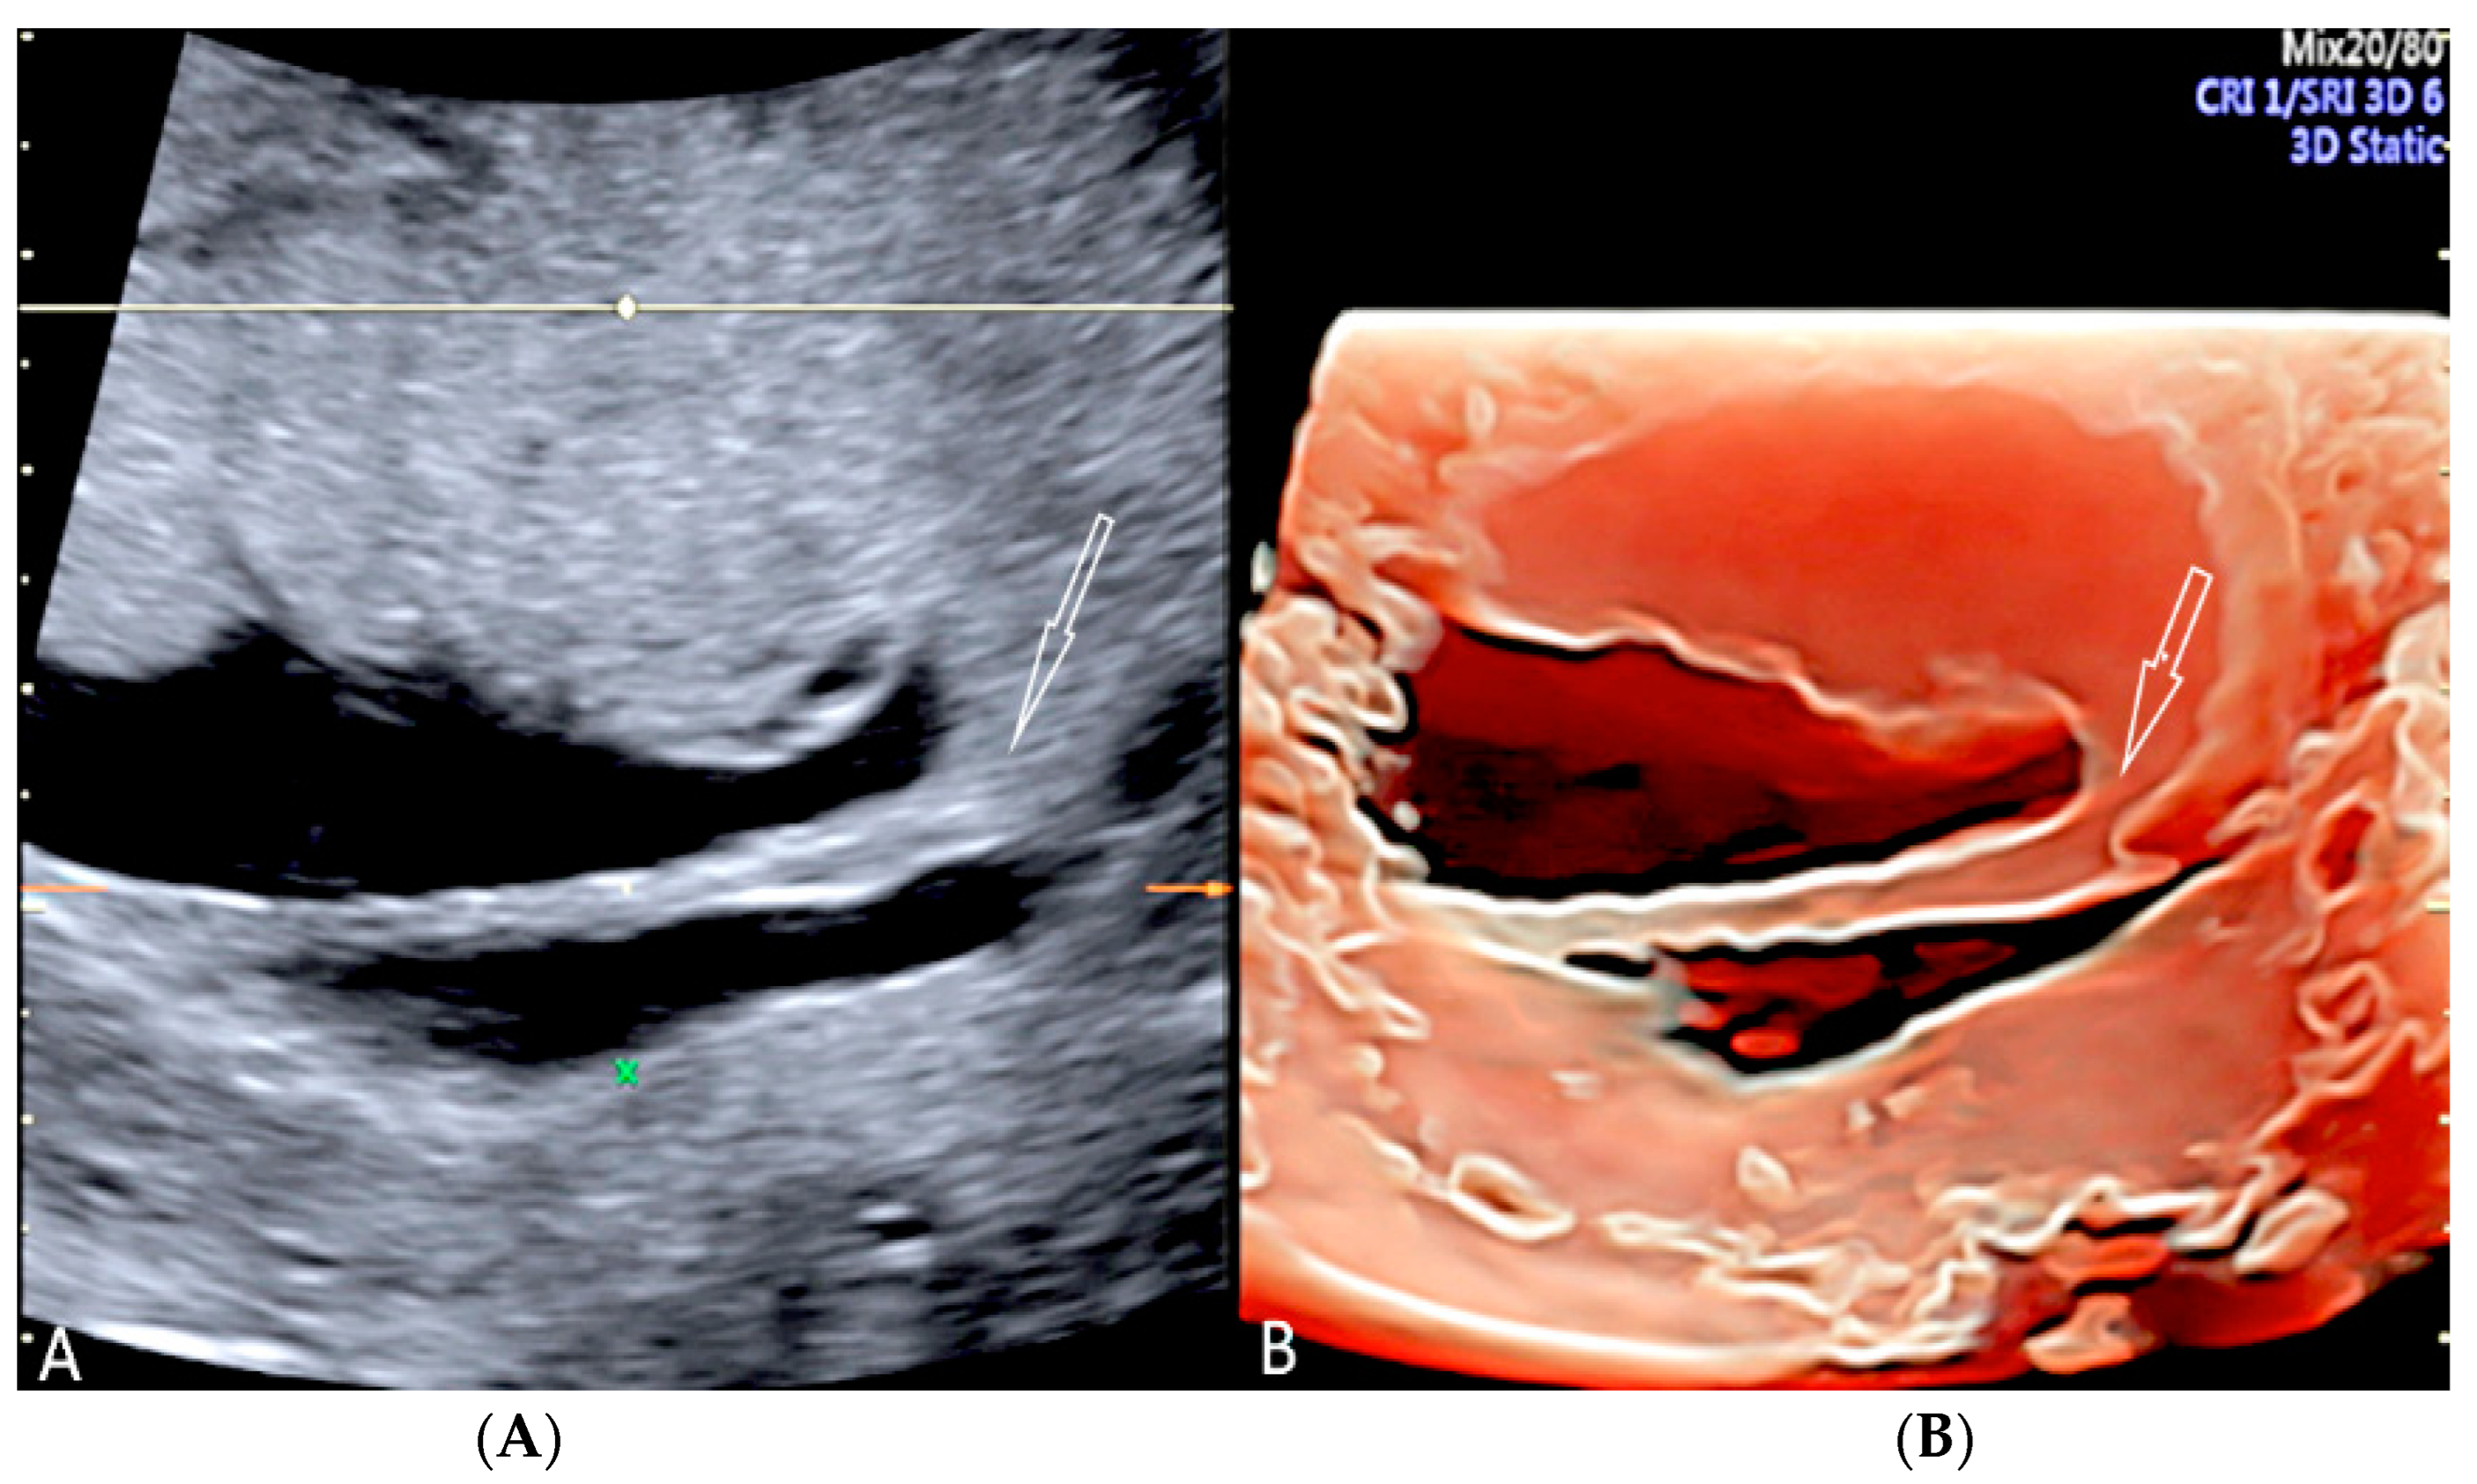

3.1.4. Circumvallate Placenta